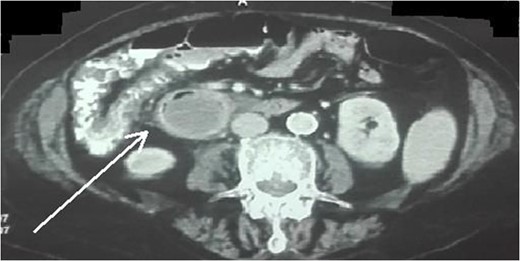

An 87-year-female patient was admitted to emergency department complaining about vomiting for the past 7 days with mild abdominal pain. The patient was hemodynamically stable, had sluggish bowel sounds and soft abdominal wall with mild tenderness. The patient also suffered from atrial fibrillation, heart failure, myelodysplastic syndrome, hiatus hernia and cholelithiasis. The findings of the laboratory tests were unremarkable. Plain chest and abdominal radiograms revealed hiatus hernia with gastric dilation (Fig. 1), a few air-fluid levels and pneumobilia, with delineation of extrahepatic and intrahepatic bile ducts by air (Fig. 2). A nasogastric tube was inserted, which drained biliary content. An abdominal computed tomography (CT) scan revealed the presence of air in the intrahepatic bile ducts, free air and leakage of oral contrast agent in the hepatic hilum and subhepatic space and an impacted gallstone in the third portion of the duodenum (Figs 3 and 4). The diagnosis of cholecystoenteric fistula and proximal gallstone ileus was set.

Abdominal CT scan (axial plane). The arrow shows the impacted gallstone.

Abdominal CT scan (coronal plane). The long arrow shows the impacted gallstone and the short arrow shows the free air and the leakage of oral contrast agent.